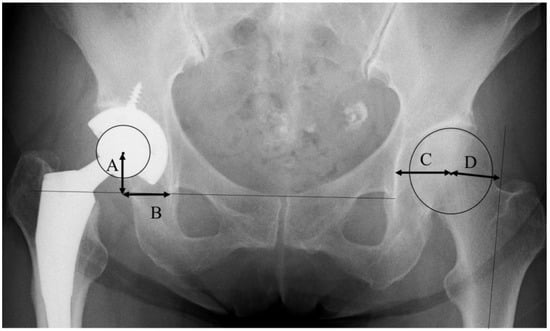

Conventional anteroposterior radiographs of the pelvis, including both hips and cross-table lateral views of the hip, were obtained to check the implant fixation. The pre-operative and post-operative leg length discrepancy (absolute value), and subsidence of the stem, were examined with anteroposterior radiographs. The global femoral offset (FO) was measured, with reference to a previous report by Sarwar et al. [14], by the addition of the distance between the longitudinal axis of the femur and the center of the femoral head, and the distance from the center of the femoral head to a perpendicular line passing through the medial edge of the ipsilateral teardrop point of the pelvis (Figure 1). The cup position was decided in reference to a previous report [18]. The center of the cup was determined by the intersection of two perpendicular diameters. The vertical center of rotation (V-COR) was defined as the vertical distance from the center of the femoral head to the inter-teardrop line (Figure 1). The horizontal center of rotation (H-COR) was defined as the horizontal distance to the teardrop, which is parallel to the inter-teardrop line (Figure 1) [18]. The vertical shift (V-shift) was defined as the difference in V-COR between the affected hip and the contralateral normal hip [18].

Figure 1. The definition of radiographic parameters with reference to a previous report [13,14,17]. (A) Vertical center of rotation (V-COR). (B) Horizontal center of rotation (H-COR). (C + D) Global femoral offset (FO).